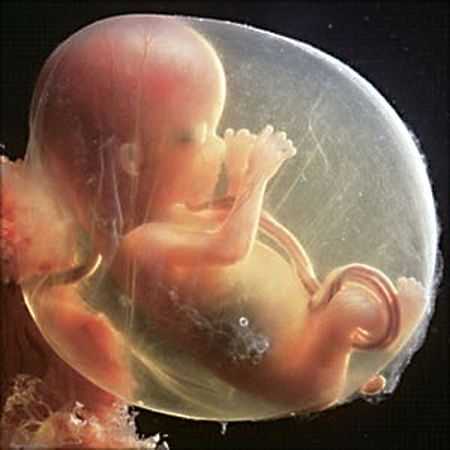

Фото:

На этой стадии снимок УЗИ уже может продемонстрировать пол малыша и показать степень и состояние его развития.

На 12 неделе при помощи УЗИ уже можно с высокой точностью определить пол будущего ребенка, а также увидеть некоторые его очертания.

Именно в это время плод уже обретает глазки, которые все еще продолжают оставаться в закрытом состоянии. Начинается процесс по формированию так называемого внутреннего уха.

Плод уже способен самостоятельно различать движения и сильную вибрацию. При прохождении планового УЗИ можно заметить очертания маленького личика, хоть череп еще не приобрел необходимую форму.

На данном этапе уже может просматриваться не только пол будущего ребенка, но и его формирующейся скелет.

В этот период он состоит только лишь из небольших хрящиков, однако уже идет их активное окостенение. У ребенка начинают постепенно разделяться между собой пальчики, появляются первые ноготки.

Фото плода на 12 неделе беременности (возраст плода 10 недель)